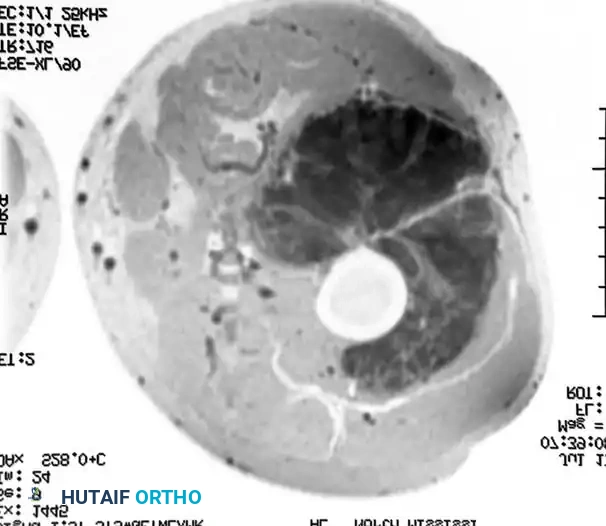

Figure 1: Axial MRI demonstrating a large, lobulated soft-tissue mass within the musculature of the thigh. The heterogeneous signal intensity and lobulated architecture are characteristic of an extraskeletal myxoid chondrosarcoma prior to therapeutic intervention.